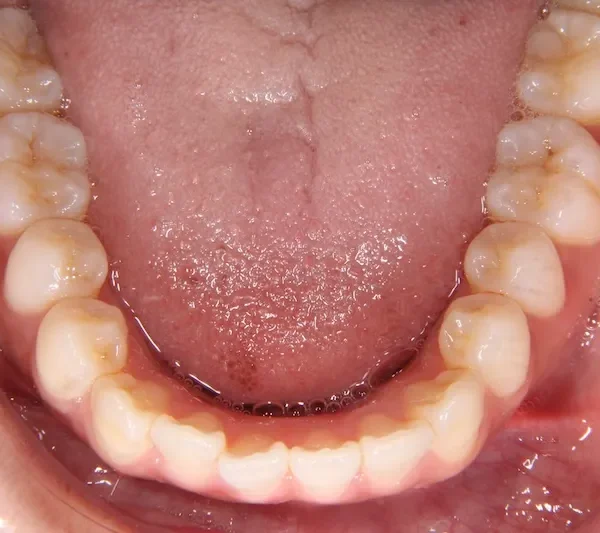

初診時

初診時年齢 19~29歳 (女性) 主訴 前歯で物が噛みちぎれない

診断名 開咬・上顎前突 装置名

状態 出っ歯(口元が出ている/上顎前突)

前歯で噛めない(開咬/オープンバイト)

前歯で物が噛みちぎれないを主訴に来院された患者様です。

非抜歯で、オリジナルリンガルアーチと歯科矯正用アンカースクリューを用いて治療しました。

治療回数15回、1年の治療期間で矯正治療を終了しました。

主訴が改善され、ご満足頂きました。